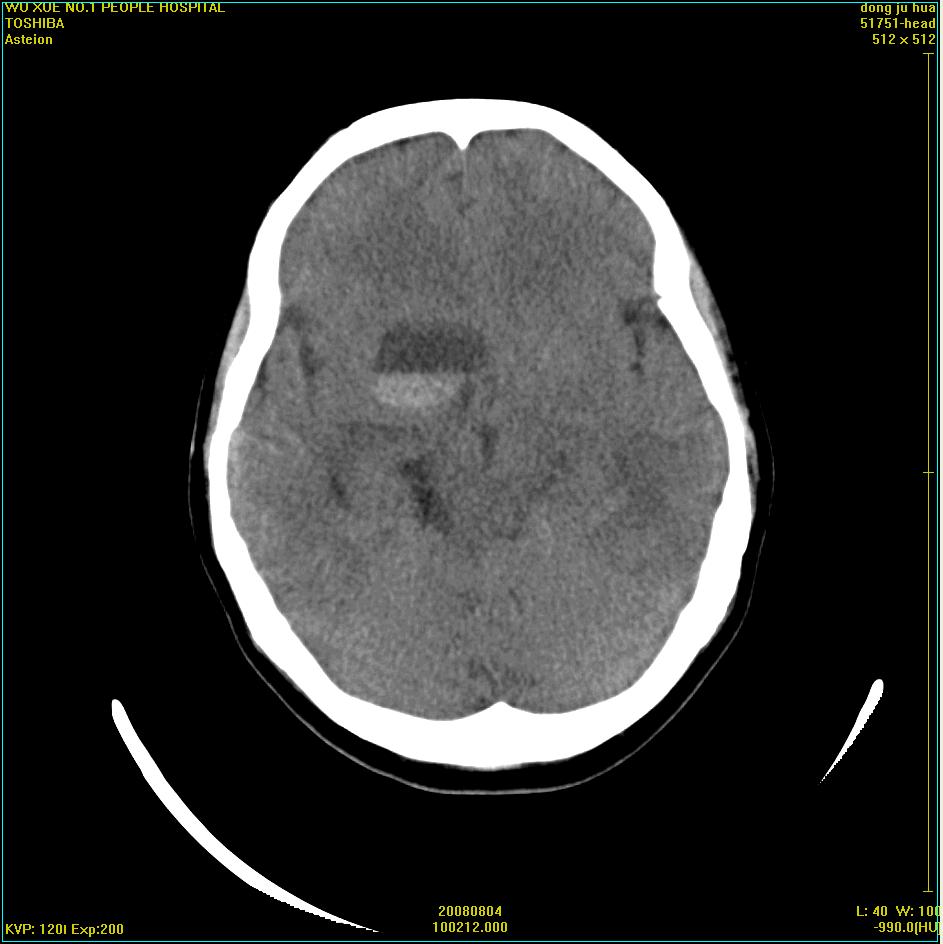

标题: CT15022:女,45岁。右侧桥小脑脚区三叉神经鞘膜瘤,已做手 [打印本页]

标题: CT15022:女,45岁。右侧桥小脑脚区三叉神经鞘膜瘤,已做手

患者,女,45岁。四年前在我院做ct诊断为右侧桥小脑脚区三叉神经鞘膜瘤,已做手术。今复杳。请大家看看

考虑三叉神经鞘膜瘤术后复发并瘤体内出血。

三叉神经鞘膜瘤术后复发并瘤体内出血

考虑慢性扩张性血肿吧!请大家再看看,发表高见!

四年前做的手术,为什么大家不考虑慢性颅内血肿呢?

考虑慢性颅内血肿?症状体征有多少?能否发上?